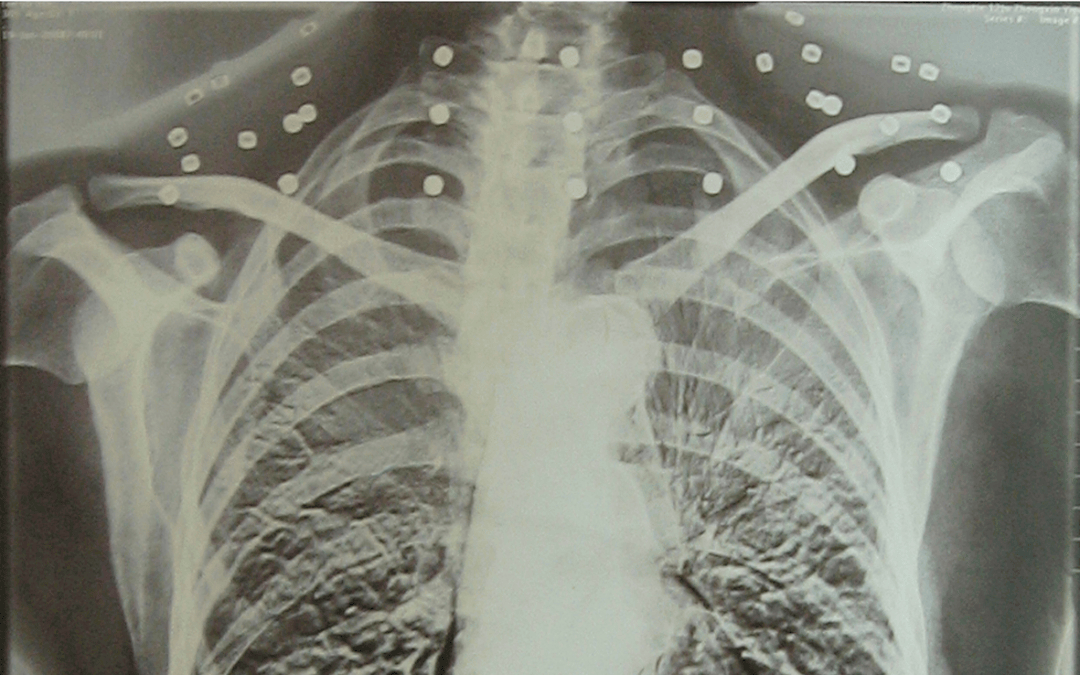

“老先生,您把项链取下来再做CT”

“老先生 您要把项链取下来再做CT” “我从来没戴过项链 你看会不会是弹片?” 这张照片 是今年82岁的吴以先老人 拍摄的一张CT照 20年前 吴以先在一次做CT检查时 医生误以为他戴了项链 于是提醒要取下来再做检查 但实际上是 吴以先的颈部和腹部 共分布着33枚弹片 无意间的对话 揭开了吴以先老人 一段不平凡的往事 展开全文 1965年 吴以先是一名铁道兵 作为中国后勤部队 一支队三大队十六连的重机枪手 参与了援越抗美战役 一天,防空警报突然响起 美军即将进行轰炸 担任...